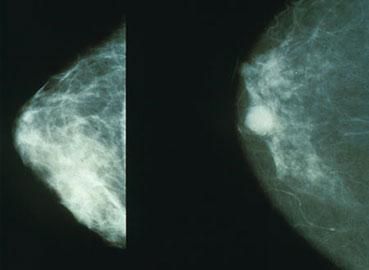

Mammograms like these can pick up breast lumps before they can be felt. The right hand image shows a potentially cancerous lump.

(Photo credit: morning2k, Wikimedia Commons)

To treat cancer successfully, it is important to detect the problem as quickly as possible, before the tumour metastases. Unfortunately it often isn’t easy to detect cancers as they grow.